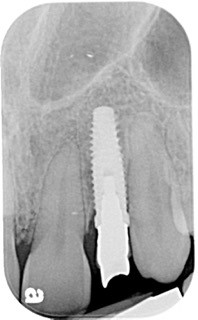

Karen is 64 years old, and her medical history is non-contributory. She, too, requires an implant at tooth #10 because of a tooth fracture from mastication. The existing tooth was deemed non-restorable. There is no periapical infection and a healthy periodontium. An implant was planned as the replacement treatment.

Following four months of healing, Karen was appointed in my office for the final restoration of the implant. The provisional was removed, without anesthesia, and the implant impression post was secured to the newly healed implant. The restorative process was uneventful, and a ceramic restoration and gold post were placed.